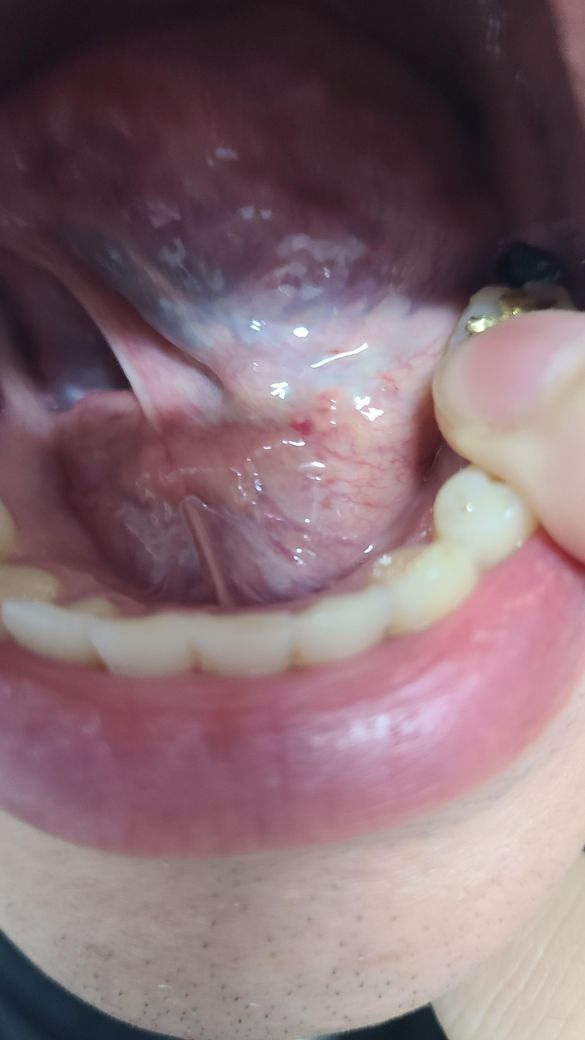

혓박 밑에 빨간 점들은 있어 질문 드립니다

양치하다가 혓바닥 밑에 빨같에 점들이 보여 질문드려요 지금 충농증 밑 임파선욤으로 치료를 받고 있습니다 다른 이상이 있는게 아닌지 궁굼 합니다

크게 문제가 잇는건 아니고 혀 밑에 자극을 받아서 피가 고인거 같습니다. 너무 걱정은 안하셔도 될것같습니다.

혓바닥에 빨간색 점이 생기는 것은 염증 반응 혹은 면역력 결핍 등이 원인이며 시간이 지나면 괜찮아질겁니다.

혀 밑에는 굉장히 다양한 조직들이 있는데요 사진상으로 특별히 이상소견은 관찰되지 않아 걱정하지 않으셔도 될 것 같습니다. 다만 추후에 통증이 발생한다거나 해당 부위가 커질 경우에는 치과에 내원해보시는 것을 추천드립니다.

구강내의 점막조직은 외부자극에 쉽게 손상받을수 있습니다 면역력이 약해지면 더 쉽게 손상될수 있습니다.

구강의 점막은 쉽게 재생이 되기 때문에 1주일정도 되면 아물게 됩니다 충분한 휴식을 취하시고 해당부위를 자극하지 않는것이 좋습니다